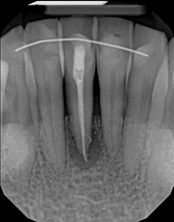

The patient was told by a specialist that the root canal failed, the only option was extraction and an implant. She did not want to do that; she wanted to keep her tooth, after all, it is her front tooth. She found us. We performed an apical microsurgery with the laser. The tooth was saved and is still functioning. This is a poor area for an implant, so much better to save the tooth.